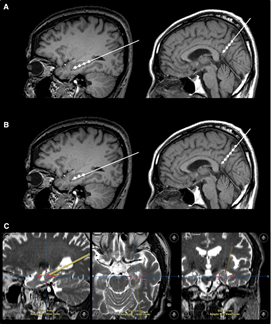

2023年1月24日,國(guó)際學(xué)術(shù)期刊Movement Disorders (運(yùn)動(dòng)障礙)發(fā)表一篇研究性文章。研究者從胎兒中腦分離制備出多巴胺神經(jīng)祖細(xì)胞,移植到患者的大腦中。設(shè)計(jì)方案:給15名患者(年齡<70歲)注射了三種劑量的細(xì)胞量(4×10*6,12×10*6,40×10*6細(xì)胞),隨后進(jìn)行12個(gè)月的隨訪。研究結(jié)果顯示:低劑量組的運(yùn)動(dòng)能力恢復(fù)效果為11.6%,中劑量組為26%,高劑量組為40%。此外,沒有副作用,如出血、免疫排斥、炎癥和腫瘤形成。